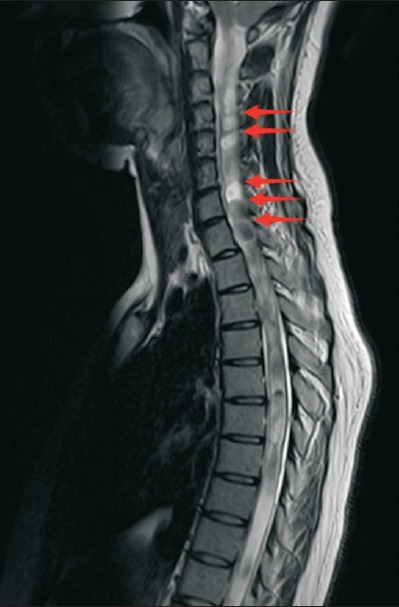

Chiari malformation type I (CMI) is a structural abnormality characterized by cerebellar tonsil herniation through the foramen magnum, often leading to disrupted cerebrospinal fluid dynamics and syringomyelia. While CMI commonly presents with occipital headaches and neck pain, atypical manifestations, such as bilateral foot drops, are exceedingly rare. We describe a 37-year-old female patient presenting with bilateral foot drop, which was later established to be caused by syringomyelia secondary to CMI. Magnetic resonance imaging revealed an 8 mm tonsillar descent and a syrinx extending to the conus medullaris. The patient refused surgical intervention and opted for conservative management; partial functional recovery was subsequently observed. This report emphasizes the importance of recognizing rare neurological presentations of CMI. To our knowledge, this is the first documented case of CMI with syringomyelia presenting as a bilateral foot drop.